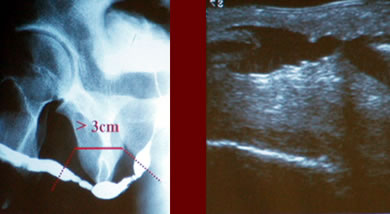

Дорсальная

уретропластика трансплантатом слизистой щеки

Стриктура уретры более

3-х см. |